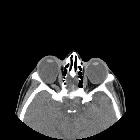

- coloboma with a cyst (microphthalmia with cyst): results from the proliferation of the embryonic retina with potential extrusion of the vitreous posteriorly into the cyst (thus microphthalmia). The cyst may become discontinuous from the eye, be larger than the eye, and may cause proptosis

In posterior ocular coloboma, on CT or MRI, the affected globe is usually small with a focal posterior defect in the globe with vitreous herniation . A retrobulbar fluid-density cyst may be present .